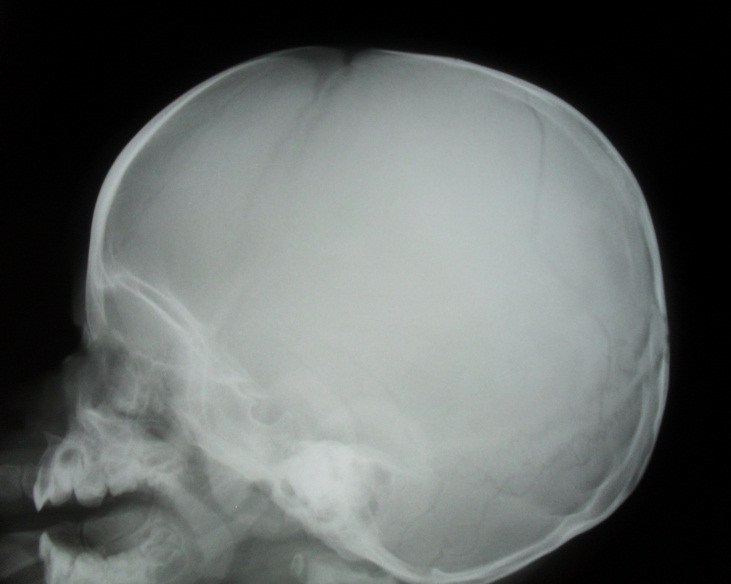

Анатомия детского черепа: Рентгеновские снимки и описание